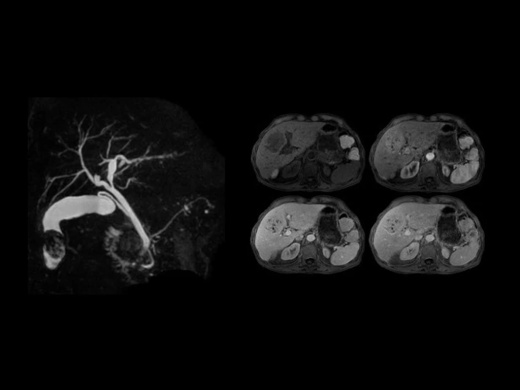

Стандартный комплект приложений SIGNA Works включает в себя решения для визуализации с использованием множества различных контрастных веществ, двухмерных и трехмерных данных, а также функции для коррекции артефактов в результате движений. С SIGNA Works все инструменты, необходимые для обследования, будут у вас под рукой.

Перейдите на новый уровень с помощью дополнительных инновационных приложений из пакета SIGNA Works и оптимизируйте работу за счет лучшего качества изображений, повышенной эффективности и упрощения рабочего процесса.